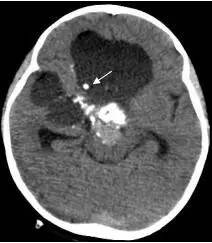

病例1:患儿男性,9岁。因反复出现意识丧失、视力下降半年收入院。入院后CT及 MRI显示颅内有形态不规则、“超大型”的颅咽管瘤,最大径约10厘米,见图1、图2。

图1.术前CT显示典型的囊性颅咽管瘤